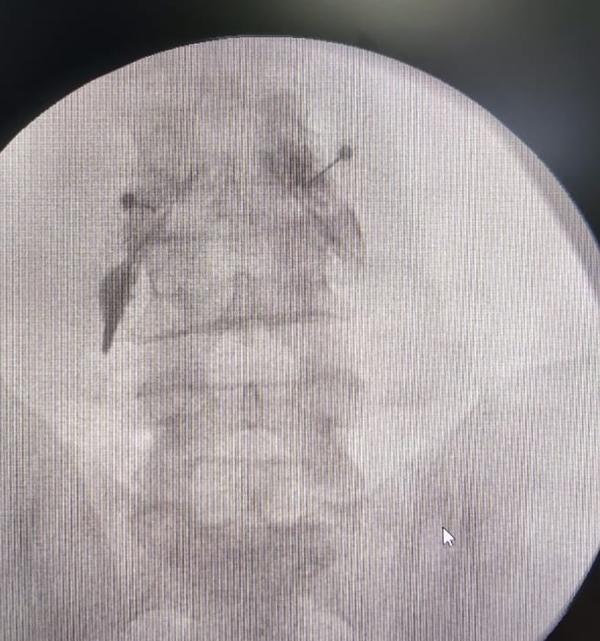

Leg Pain due to Spine issues? Not Responding to Me...

View Details

Spine Surgery is too risky !!. Spine Surgery gets ...